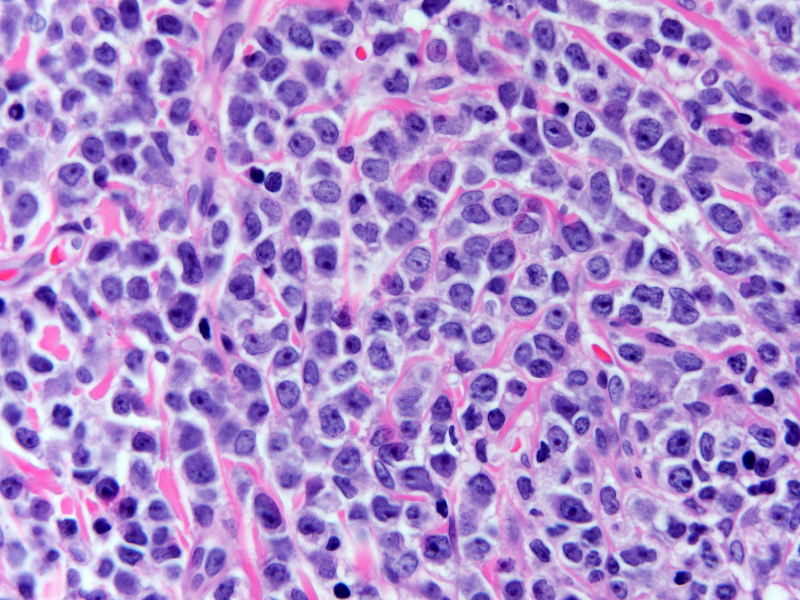

| Skin of left upper thigh mass (H&E, 600X) shows a monotonous population of large mononuclear cells with fine chromatin and visible nucleoli. | ![]() |

Excisional biopsy of the left inner thigh mass was performed. Gross inspection of the lesion revealed a surface greenish tan plaque which extended into the dermis and subcutis. Touch preparations showed a monomorphic population of large mononuclear cells with fine chromatin and scant basophilic cytoplasm. Histologic sections were fixed in either 10% buffered formalin or acetic zinc formalin. Initial touch preparation of the mass revealed a population of blasts with fine chromatin and scant basophilic cytoplasm. Histologic evaluation revealed a dense proliferation of large mononuclear cells with fine chromatin diffusely involving the dermis and subcutis. The infiltrate focally extended into the epidermis.